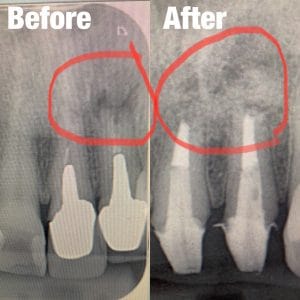

前医で根切という外科的な根の治療を受けていましたが、それがうまくいっていなく、また膿んでしまっている方の再治療をおこないむした。根切のやり直しは非常に難しいのですが、膿んで溶けてしまっていた骨の再生も確認できて経過は良好です。

またセラミックも新しく綺麗にして、歯茎の黒ずみも消失しています。

治療回数

3回(写真カウンセリングを含む)

担当:理事長 佐藤悠野